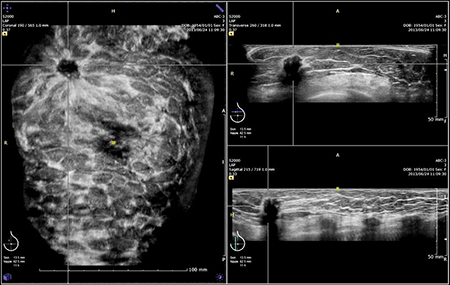

ボリュームデータ取得後は,解析専用のワークステーション上で,自由な直交3断面を切り出して観察できます。特に,広範囲の冠状断面では位置関係を把握しやすく,多発性や広範囲の病変の診断に有用です。また,過去画像との比較観察も可能です(図2)。

図2 硬癌

冠状断面にて左A領域にスピキュラを認める。